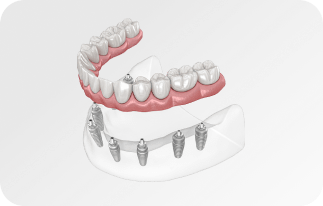

Зубы за 1 день за 5776р. в месяц

с пожизненной гарантией

По уникальной методике

БЕЗ отёков и надрезов

Установка

за 1 день